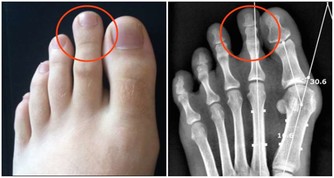

4、按摩穴位。可按揉這四個穴位:心俞穴(兩肩胛骨中間、脊梁骨和兩側大筋部位)按揉36次,左右各轉18次;腎俞穴(即兩邊腰眼),兩側各按揉36次,每一側都是左右轉各18次,對促進腿部血液循環很有好處;揉搓湧泉穴,以感覺到熱為限度,再搓揉腳趾;特別是大腳趾頭第二節有幾根汗毛的地方,叫「三毛穴」,要多揉搓,然後稍用力捏3-5次。